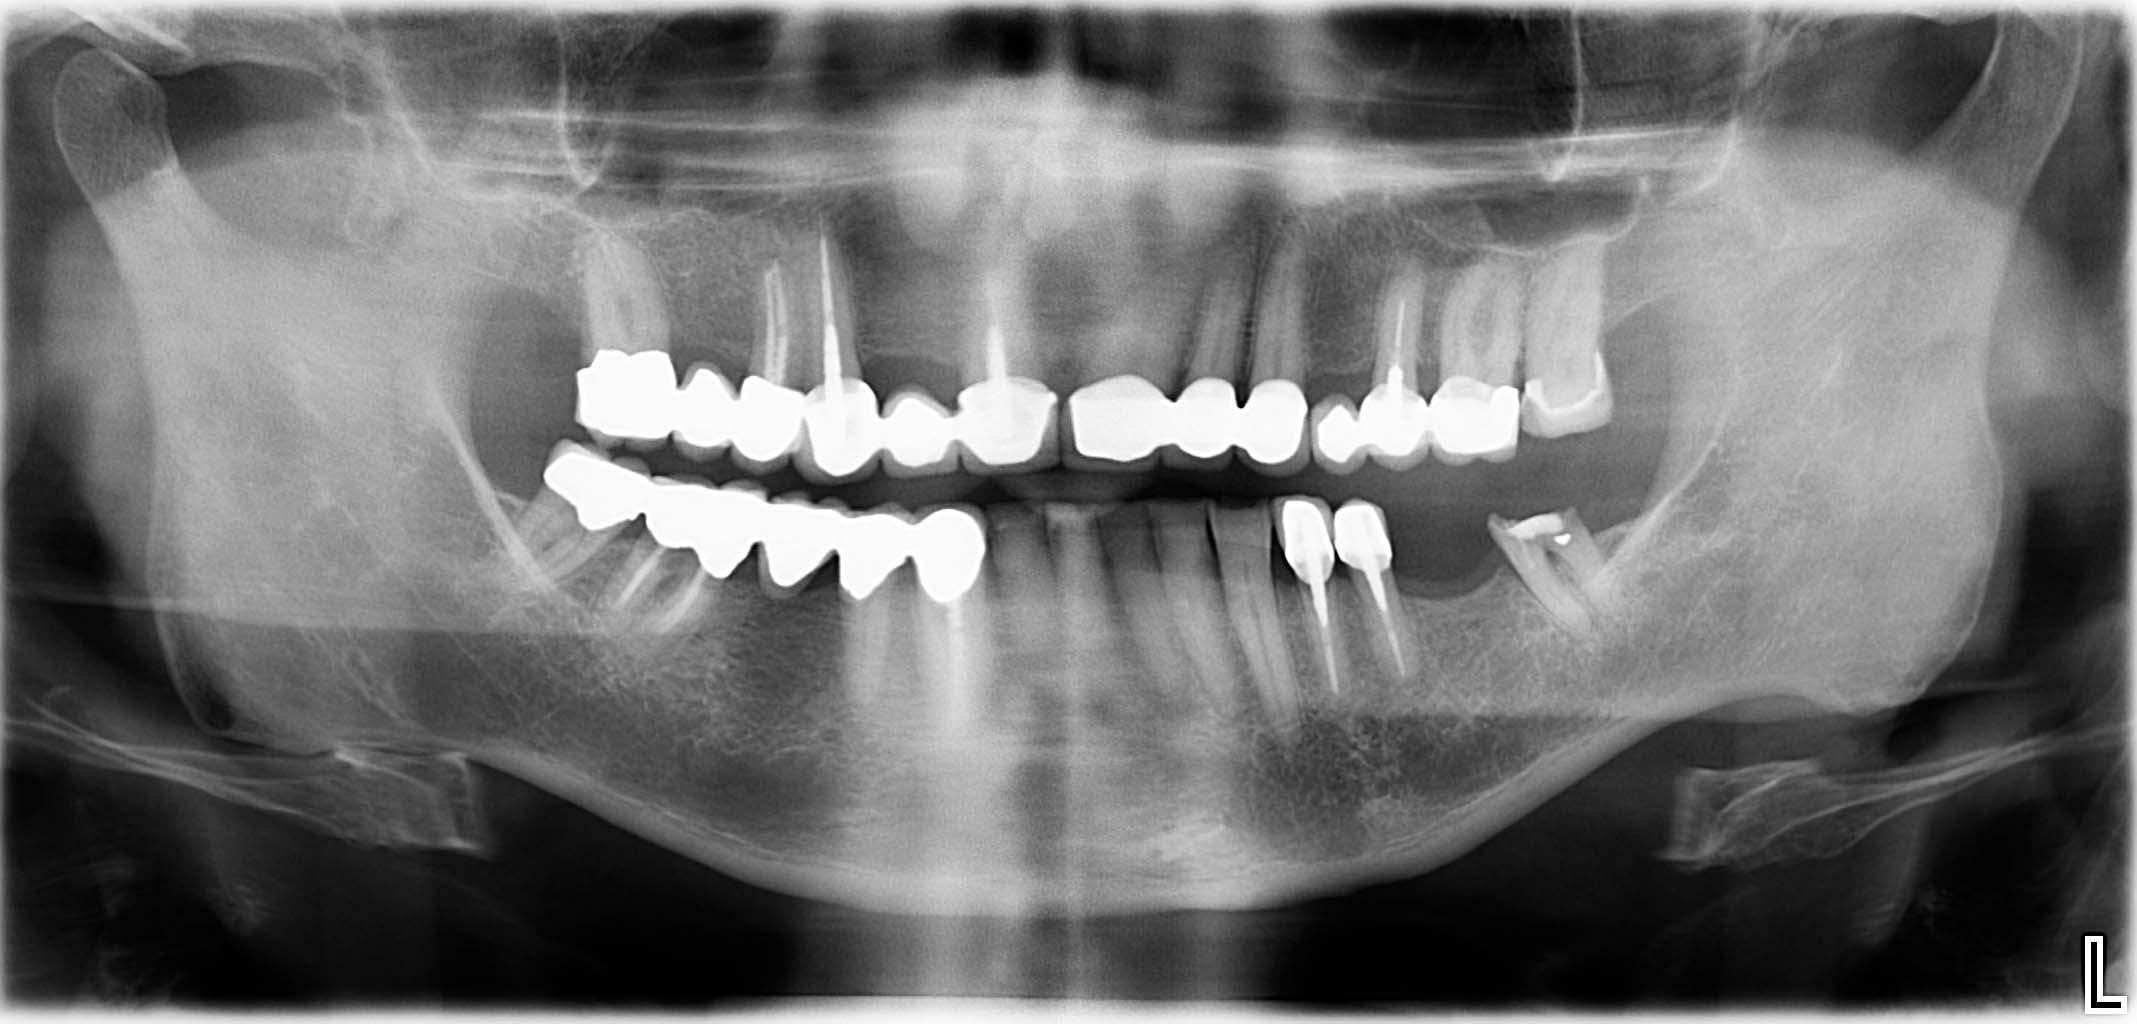

Erfolgreich implantierte Patientenfälle (klinische Fotos)